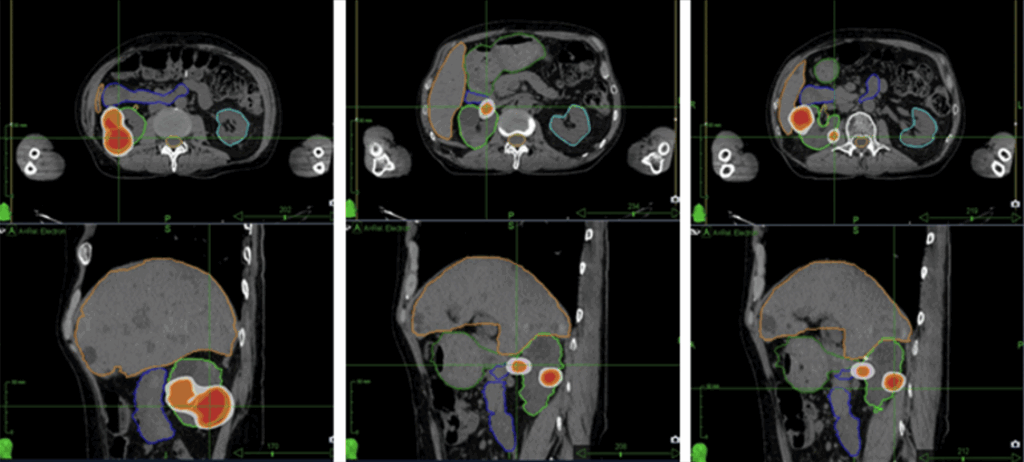

MRIFour new renal lesions identified in the right kidney (figure 1)

Figure 1: Renal lesions identified on MRIadaptive radiotherapy, and (Conventional Linac) ITV-method